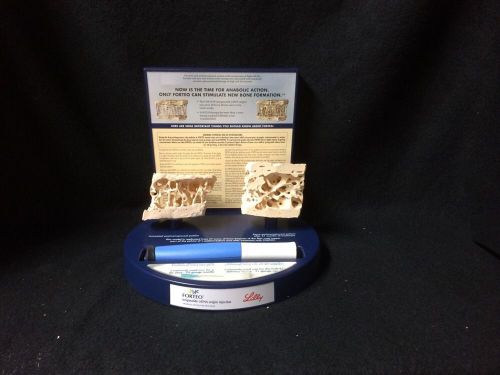

Cancellous Bone Section Anatomical Teaching Model